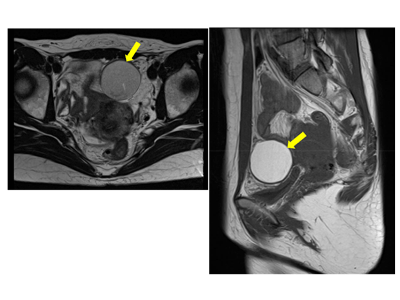

画像はリリースより

今回、荒川医師らのグループは、大網に発生した稀少部位子宮内膜症の症例を報告した。患者は37歳で、5年前に腹腔鏡下子宮内膜症性卵巣嚢胞摘出術を受けた既往があった。月経時の強い下腹部痛を主訴に同院女性診療科・産科を受診し、コンピュータ断層撮影(CT)と磁気共鳴画像検査(MRI)で下腹部に直径約4 cmの嚢胞性病変が見つかった。病歴と画像所見から子宮内膜症が疑われた。

発生部位としては腸間膜などの生殖器以外の臓器が疑われたため、大腸・肛門外科で精査のうえ、腹腔鏡補助下腫瘍切除術が行われた。腫瘍は大網の下部に存在しており、大網切除術が行われた。子宮・両側卵巣は肉眼的に正常だった。病理診断では、大網に発生した子宮内膜症性嚢胞であり、悪性所見は認められなかった。術後の経過は良好で、術後22か月間再発なく経過している。